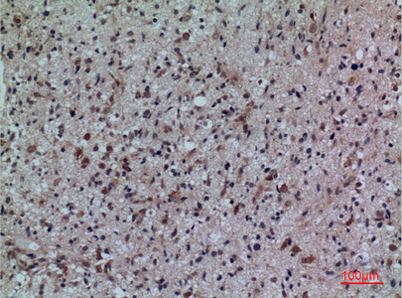

Product name: CD307 rabbit pAb

Dilutions: Western Blot: 1/500 - 1/2000. IHC-p: 1:100-300 ELISA: 1/20000. Not yet tested in other applications.

Immunogen: The antiserum was produced against synthesized peptide derived from the Internal region of human FCRL5. AA range:191-240